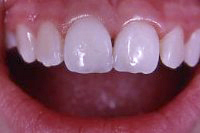

Die Abb. 1 bis 4 sollen als anschauliche Beispiele für gesunde und kranke Fundamente dienen.

Ein 31 Jahre alter Patient zeigt einen starke Zahnfleisch-Rückgang im Oberkiefer (Abb. 1 und 3) und wir beschliessen, diese Rezessionen zu behandeln.

Der Erfolg der Behandlung ist deutlich in den Abb. 2 und 4 zu sehen. Sehr augenfällig konnte die Situation um den Eckzahn im linken Oberkiefer verbessert werden (vergleiche dazu Abb. 3 vorher und Abb. 4 nachher).